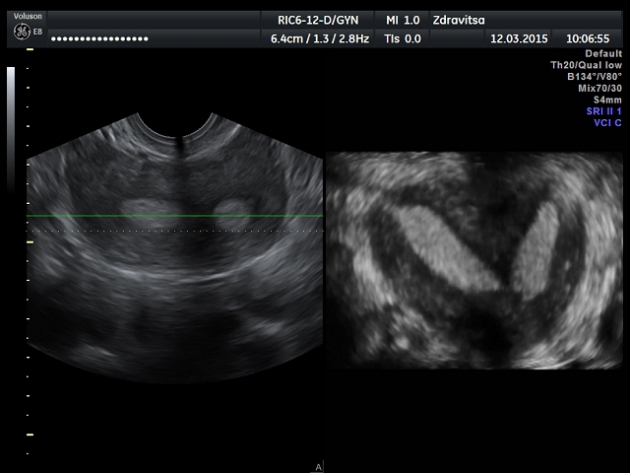

Случай №2. Девушка 22 лет, жалобы на НОМЦ по типу альгоменореи в течении последних трех месяцев.1-я фаза цикла.

1. Двурогая.

2. Седловидная